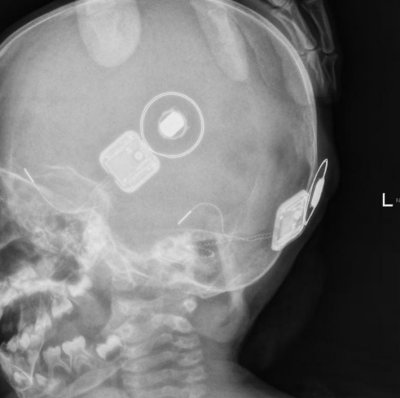

面对这四大难关——解剖结构变异、脑脊液“井喷”风险、电极定位困难、神经反应不确定性,冯永教授带领团队进行了周密的术前规划和精心的手术准备。手术中,医生在乐乐耳后打开一个微小切口,当在畸形的耳蜗上进行造孔时,正如术前预期,出现了脑脊液“井喷”。冯永教授沉着应对,待压力稍减后,凭借精湛的技术,将纤细的电极精准地植入了仅1.5圈的耳蜗内,并迅速用自体组织牢固封闭了造孔。术中神经反应监测显示,电极与听神经成功建立有效连接,这标志着手术最关键的步骤已成功完成。

手术的成功仅是第一步。约一个月后,乐乐的人工耳蜗将迎来“开机”时刻。届时,他将首次感知到这个世界的声响。尽管最初的声音可能如同“机器人说话”,但在专业的听觉言语康复训练下,他有望逐渐理解声音、学会说话,最终融入正常的社会生活。